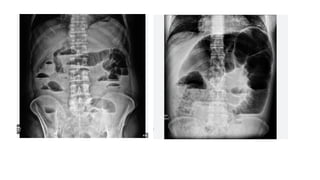

• Plain X-ray abdomen:

• (initially supine abdominal X-ray is taken; later if needed X-ray in erect posture is

taken if perforation is suspected).

• Multiple air-fl uid levels.

• Proximal the obstruction >>>>>>> Lesser the air fluid level.

• Distal the obstruction >>>>>>>>> More the air fluid level.

• Normally, three fluid levels can be seen in plain X-ray fIlm—at fundus of stomach, at

duodenum and often at caecum.

• Jejunum shows concertina effect due to valvulae conniventes (Herring bone pattern)

—by the valves of Kerckring.

• Ileum is smooth and characterless (by Wangensteen).

• Large bowel shows haustration.

• Pneumobilia (gas in biliary tree) may be due to gallstone ileus.

• Distended caecum is shown as round gas shadow in the right iliac

fossa. Dilated caecum signifies large bowel obstruction.

• Small bowel > 3 cm diameter;

• proximal large bowel > 9 cm;

• transverse colon > 5.5 cm; sigmoid colon > 5 cm are suggestive of

intestinal dilatation.